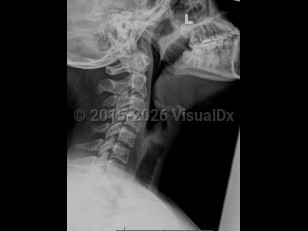

Sore throat, Dysphagia, 50-59 year old Female

EpiglottitisEpiglottitis